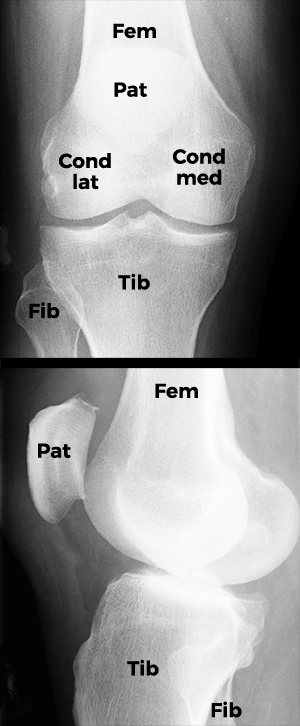

Dieses Bild zeigt Röntgenaufnahmen eines normalen Kniegelenks.

Das obere Bild zeigt das Knie von vorn, das untere von der Seite. Die Kniescheibe (Pat) [Patella] vor dem Oberschenkelknochen (Fem) [Femur] ist in der Ansicht von vorne nur zu erahnen. Gut sichtbar ist das Schienbein (Tib) [Tibia] und etwas schwächer, da erheblich dünner, außen daneben das Wadenbein (Fib) [Fibula].

Deutlich sind die beiden Condylen des Oberschenkels zu sehen, die, Schlittenkufen ähnlich, über dem Plateau des Schienbeinkopfes zu schweben scheinen. Tatsächlich sind die Condylen wie auch das Schienbeinplateau mit einer Knorpelschicht überzogen. Außerdem werden diese noch durch die Menisken getrennt. Diese sind, wie auch die Bänder im Röntgenbild nicht sichtbar – wohl aber in der Kernspin-Tomographie.

Erscheint der Gelenkspalt im Röntgenbild sehr schmal oder ist er gar aufgehoben, so ist das Folge von Abrieb an Knorpel und Meniskus, also von Kniegelenk-Verschleiß [Gonarthrose].